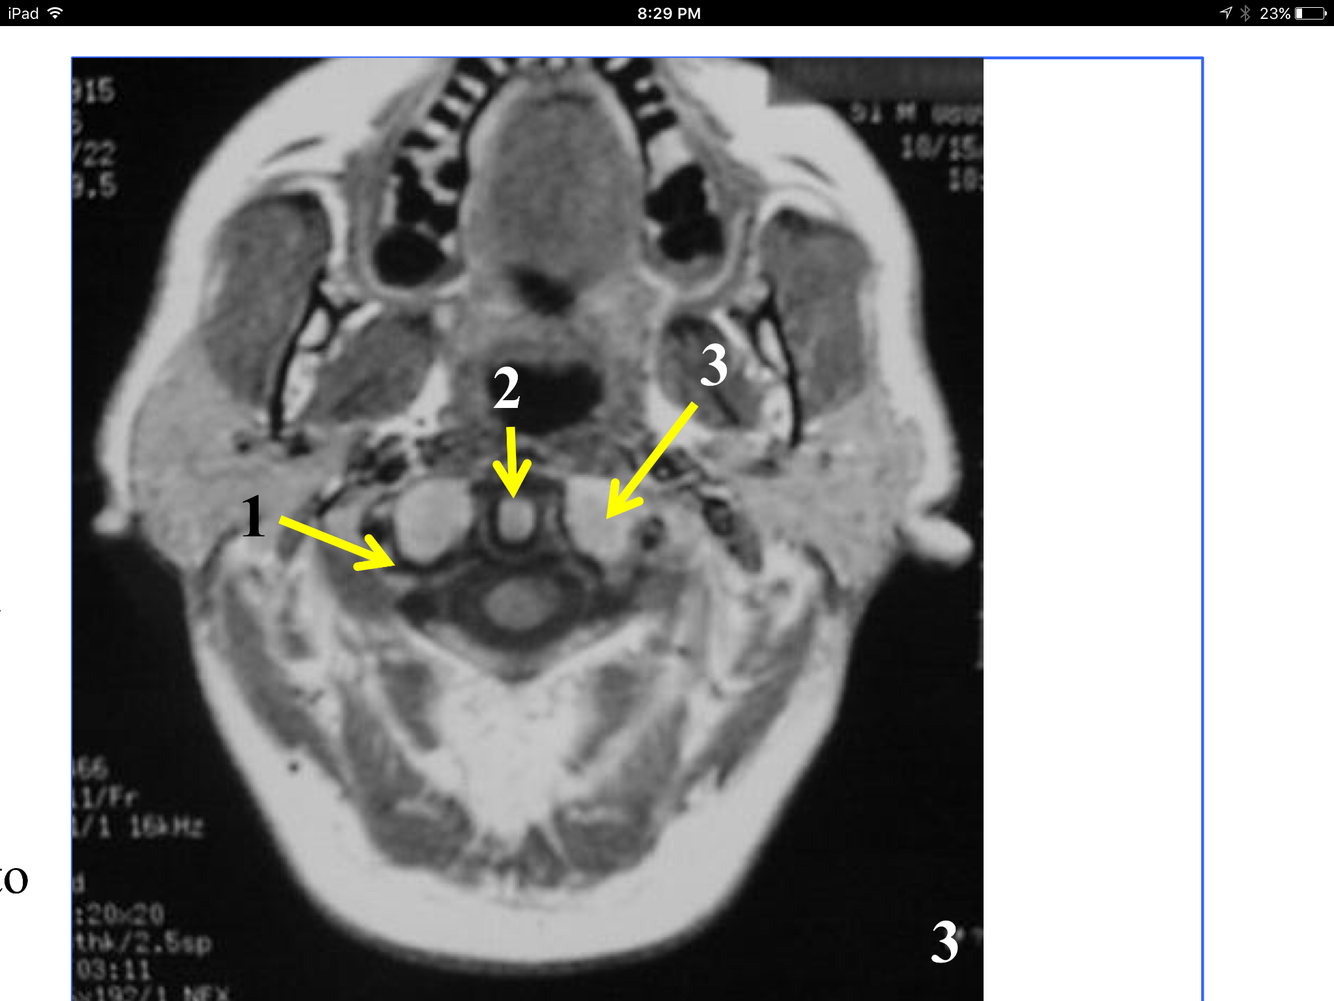

* Just superior to atlantoaxial joint

**10. Rt & Lt vertebral arteries**